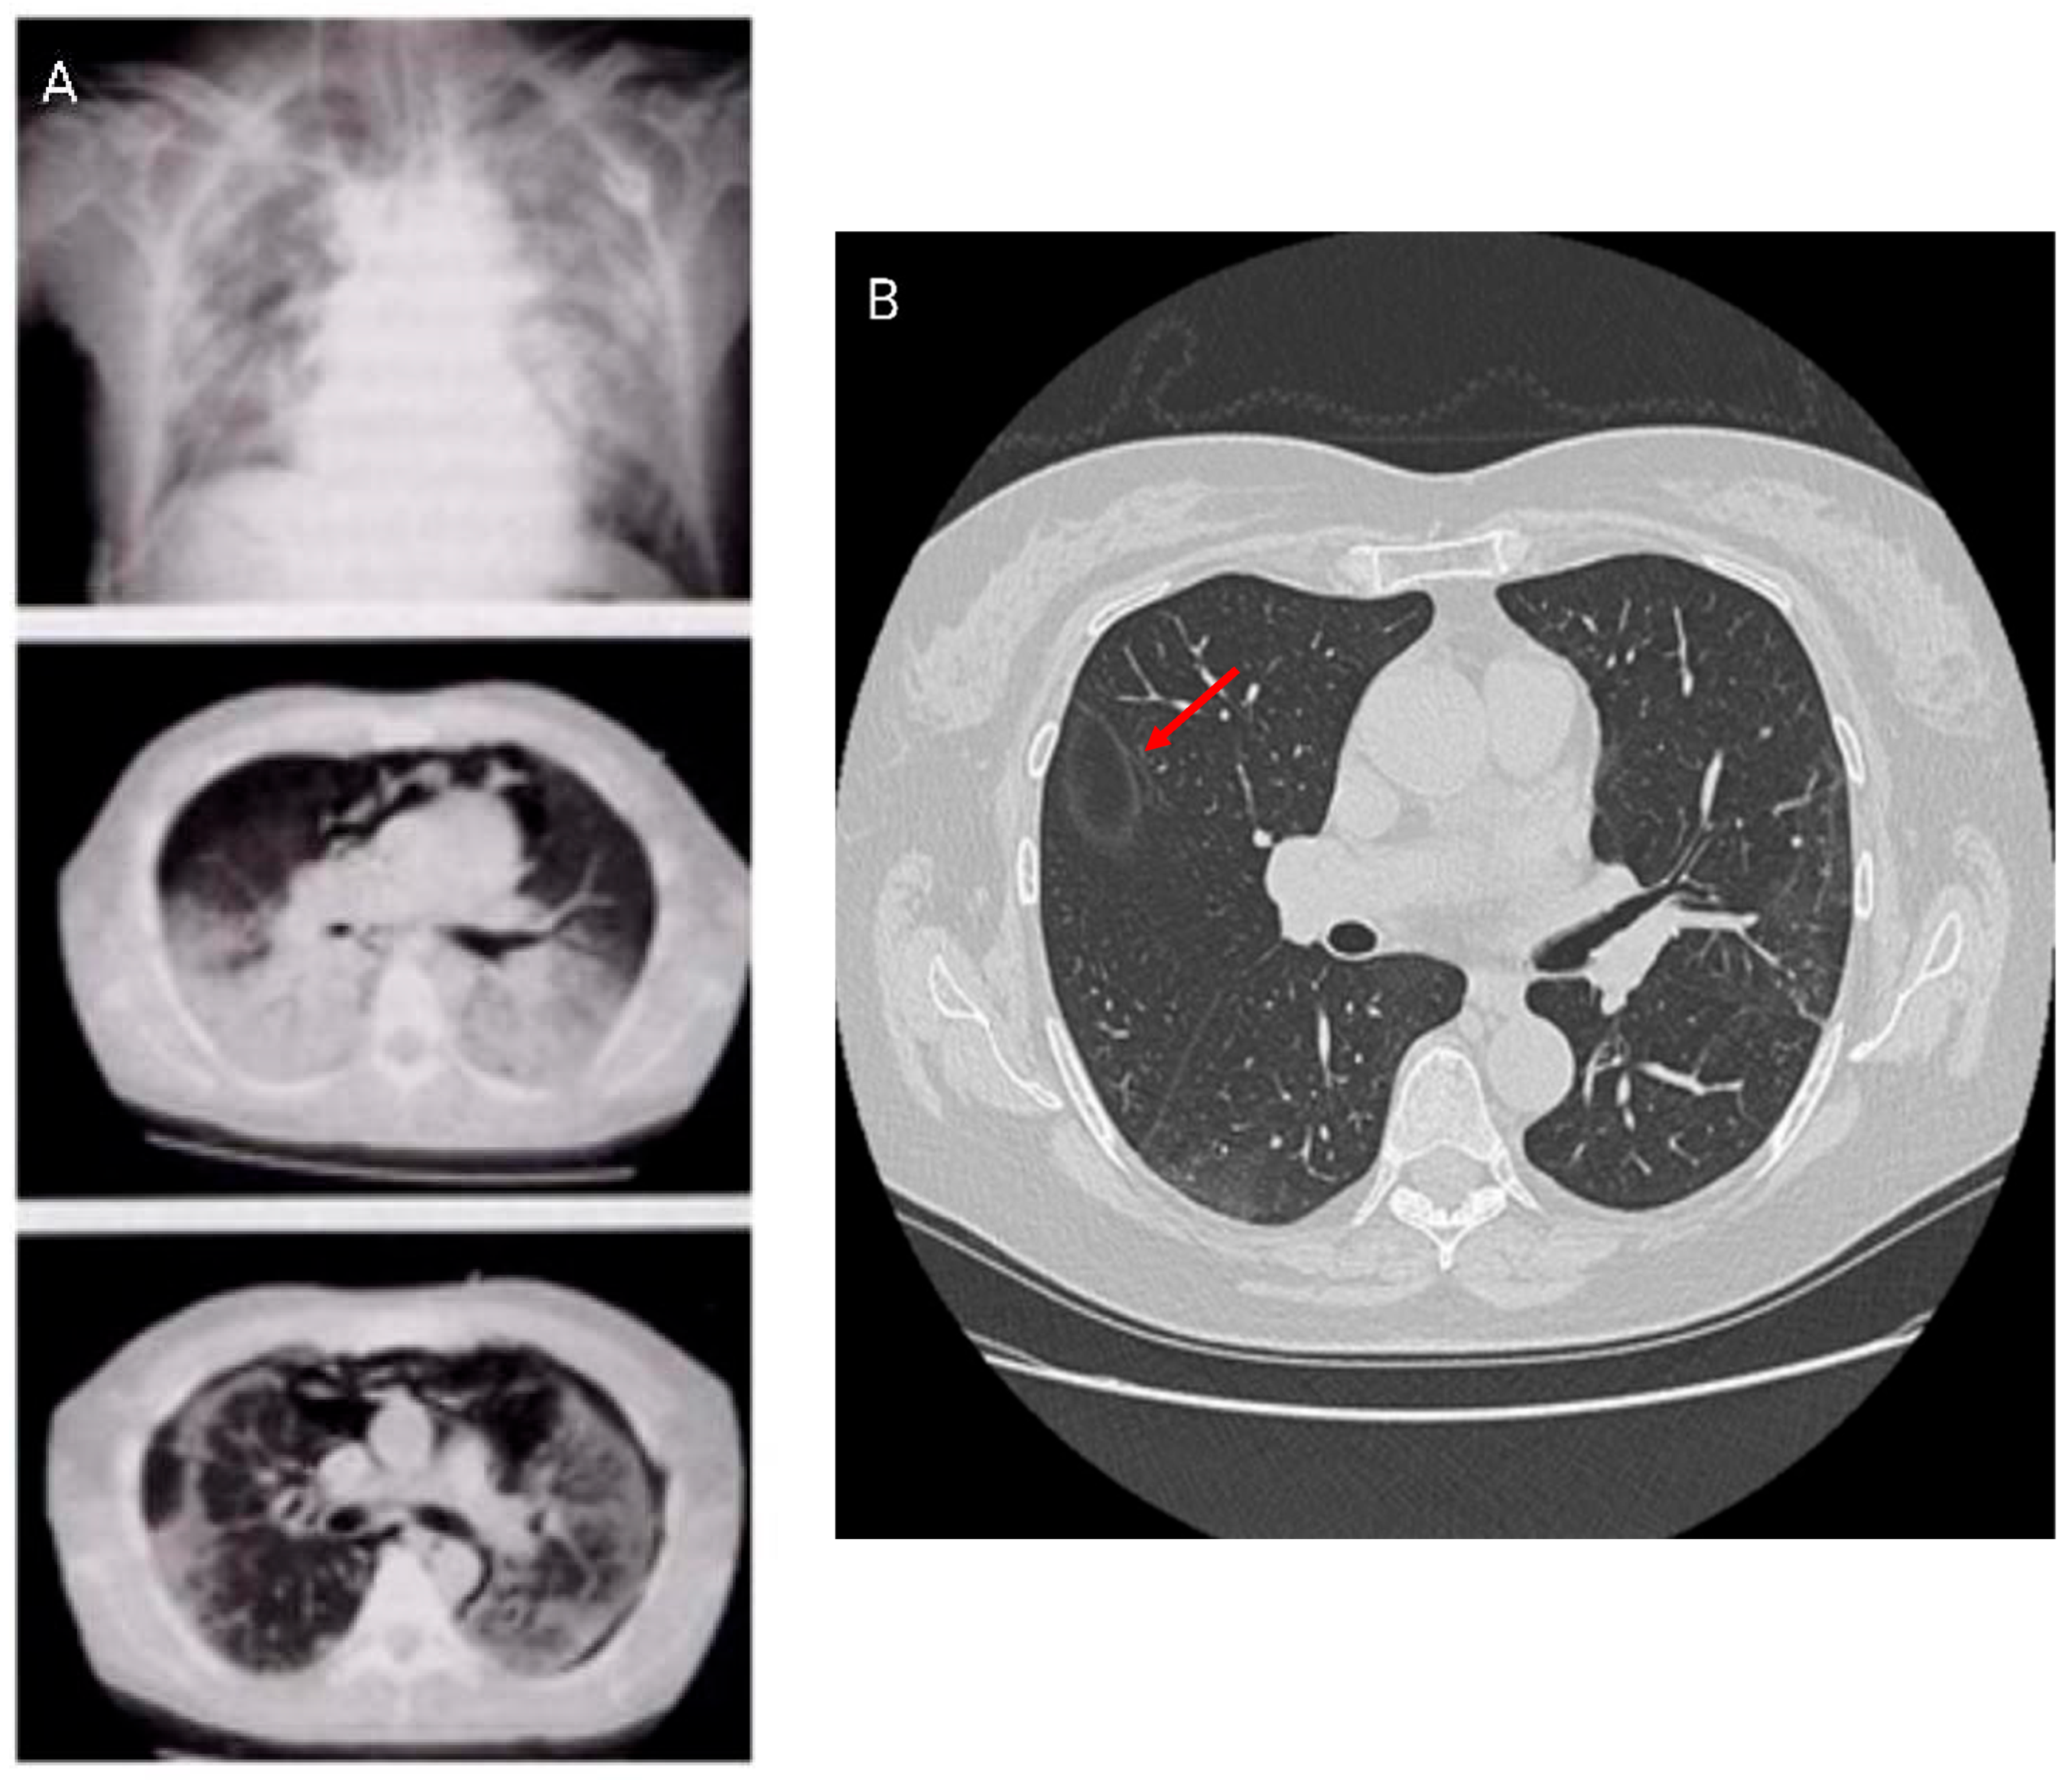

HRCT is the preferred imaging modality for the diagnosis, management, and monitoring of post-COVID-19 ILD. HRCT scans identify the location and distribution of lung abnormalities, which can be bilateral, peripheral, or mid- to lower-lobe parenchymal changes. The most common HRCT patterns are ground-glass opacities, indicative of alveolar spaces filled with cells or fluid, alveolar wall thickness, and a reticular pattern, typical of ILD [20]. The extent of HRCT abnormalities correlates closely with symptom severity and TLC reduction, in agreement with National Institute of Health findings [18]. HRCT allows: (1) early fibrosis detection; (2) treatment guidance, including use of antifibrotic drugs; and (3) prognostic assessment via serial imaging or scale evaluation [23].

A potential radiologic sign of HRCT is the atoll sign, or the reversed halo sign. The characteristic image shows a central area of ground-glass opacity surrounded by a ring of denser consolidation. This pattern can be suggestive of organizing pneumonia (OP) and is found in a variety of pulmonary diseases like fungal infections in neutropenic patients, granulomatosis with polyangiitis, and various tumors such as lung adenocarcinoma and lymphoma. Histopathology shows that the central ground-glass opacity corresponds to septal inflammation, while the peripheral ring relates to inflammation of the alveolar ducts or airspaces.

Further, the crazy paving pattern, characterized by ground-glass opacities with interlobular and intralobular septal thickening, has been observed in HRCT imaging associated with COVID-19. HRCT patterns are non-specific because they can be found in alveolar proteinosis, ARDS, and other interstitial pneumonias [24,25]. Studies have identified different HRCT patterns between early and more advanced disease stages. The latter showed an increase in pleural changes including subpleural lines and effusions. HRCT patterns are shown in Figure 3.

Figure 3. Radiological imaging in COVID-19 infection. HRCT patterns in Acute Respiratory Distress Syndrome (ARDS) (A) and in subacute phase with atoll or reversed halo sign ((B) arrow).